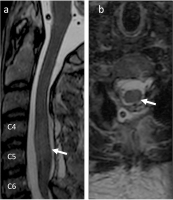

Traumatische spinale Subarachnoidalblutung: ein anschaulicher Fall mit Literaturübersicht // Traumatic spinal subarachnoid hemorrhage with spinal cord compression – a case report and literature review